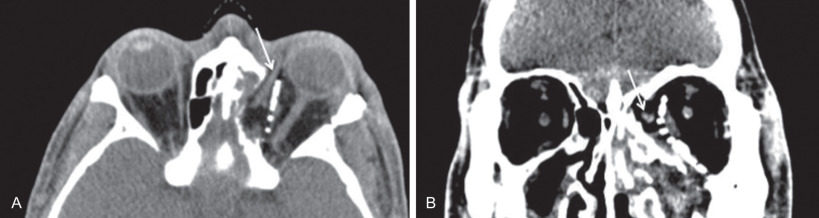

Due to the high incidence of internal carotid injuries in high sub-cranial fractures, it is our protocol to perform CT angiography on all panfacial injuries. High-definition, thin-slice CT scans with three dimensional reconstructions are invaluable in evaluation, surgical planning, and subsequent long-term management of panfacial fractures. Additionally, intraoperative CT scanning, when available, can be useful for assuring accurate placement of orbital implants at the time of surgery ( Fig. 1.19.5 ). Although stereotactic navigation and computer generated models are useful in secondary corrections of complex cases, they are not usually readily available for acute treatment.